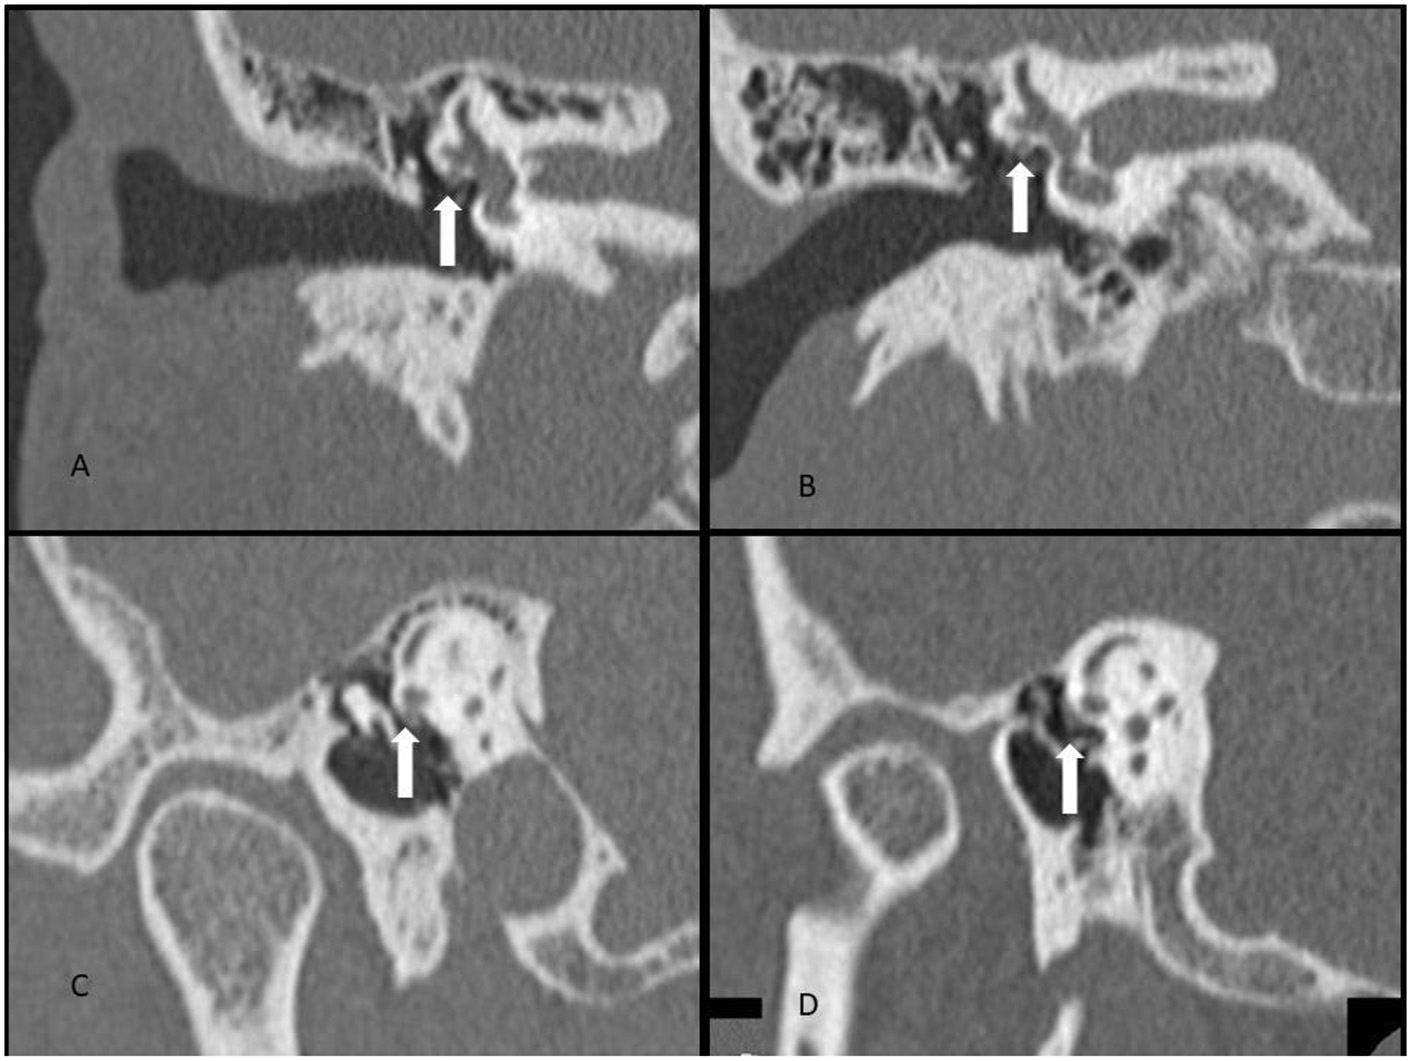

Fallopian canal dehiscence was not systematically recorded, but it seems that all patients had fallopian canal dehiscence noted at surgery. We believe that fallopian canal dehiscence is a necessary part of the anatomy for HSC-FND to become “active.” As noted in Figure 1, there are concomitant defects of the HSC and the fallopian canal at the Oval Window. The concept being the horizontal canal defect leads to pressure changes or an intermittent leak around the facial nerve. If there was no fallopian canal dehiscence, then there would be no means for fluid/pressure movement.

Figure 1

CT scan demonstrating (A) HSC-FND on coronal imaging, (B) normal HSC and facial nerve anatomy on coronal imaging, (C) HSC-FND on Poschl imaging, and (D) normal HSC and facial canal on Poschl imaging.

The CT scans of our series of HSC-FND do not identify any erosive process such as cholesteatoma as the source for the dehiscence (see Figure 1 for examples of HSC-FND compared to normal CT scans.). The overlying tympanic segment of the facial nerve suggests a probable anatomic defect that may be of congenital or developmental origin, perhaps due to the reduced otic capsule bone volume as noted by Park et al. (19). Among the 16 cases, 10 (63%) reported the onset of their symptoms immediately after trauma. This is consistent with the second event observation seen with many SSCD patients and suggests a similar pathogenic mechanism for the production of symptoms (12). However, the cause for this bony defect and symptoms onset awaits further investigation.

In our series, the HSC-FND was most evident on both the coronal and Poschl view (a projection perpendicular to the long axis of the petrous bone, at an angle of 45 degrees with the sagittal and coronal planes). This orientation allowed visualization of a cross section of the facial nerve and the bony septum with the horizontal semicircular canal. The axial, sagittal, and Stenvers projections did not demonstrate the dehiscence with the same level of confidence.